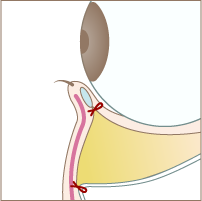

Step 03

隔膜と眼窩脂肪を一塊として引き下げ、骨膜に縫合します。

Step 04

切開した部分を縫合して完成です。